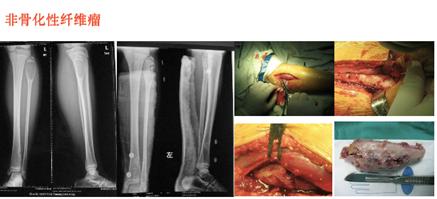

常见的良性骨肿瘤有骨样骨瘤、骨软骨瘤、软骨瘤等,原发性恶性骨肿瘤常见的有:骨肉瘤、软骨肉瘤、恶性纤维组织细胞瘤、尤因肉瘤、恶性淋巴瘤、骨髓瘤、脊索瘤等。

转移性骨肿瘤常见来源有:乳腺癌、前列腺癌、肺癌、甲状腺癌、肾癌。还有类肿瘤性的其他病损,包括骨囊肿、动脉瘤样骨囊肿、嗜酸性肉芽肿、骨纤维结构不良。其中青少年好发的恶性肿瘤最常见的是骨肉瘤、尤文肉瘤。